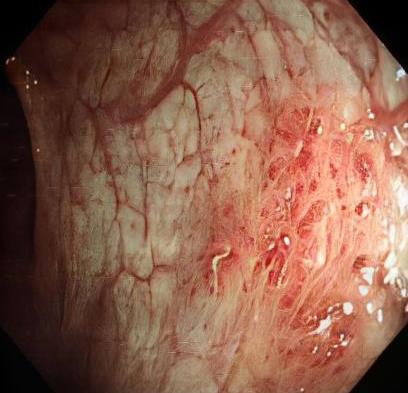

• 获得性免疫缺陷综合征合并马尔尼菲篮状菌导致肠道感染的内镜下表现(附6例报告)

2026, 32(3):84-88. DOI: 10.12235/E20250461

摘要 (32) HTML (27) PDF 3.50 M (26) 评论 (0) 收藏

摘要:目的 探讨获得性免疫缺陷综合征(AIDS)合并马尔尼菲篮状菌(TM)感染导致肠道感染的内镜下特征。方法 回顾性分析2022年11月-2024年10月于该院确诊为AIDS合并TM感染导致肠道感染的6例患者的临床资料。包括:临床症状、实验室检查、影像学检查、内镜检查和病理检查等。结果 6例患者中,男5例,女1例;发病年龄26~67岁;AIDS合并TM感染导致肠道感染患者的临床表现为:腹泻、腹痛、腹胀和恶心呕吐。其中,2例有消化道出血表现。实验室检查:6例患者外周血白细胞计数为(1.37~4.49)×109/L,血红蛋白计数为(67~99)g/L;CD4+T淋巴细胞为(1~52)个/μL,CD8+ T淋巴细胞为(61~321)个/μL,CD4+T淋巴细胞/CD8+T淋巴细胞比值为(0.01~0.18)。6例患者均行HIV RNA检测。其中,5例HIV RNA阳性。血培养:可见丝状真菌,报告显示为TM。影像学检查:6例患者CT结果可见肠系膜及腹膜后多发淋巴结肿大。内镜检查:6例患者内镜下均可见肠道病变。其中,十二指肠糜烂溃疡2例,结肠多发糜烂溃疡4例。病理检查:6例患者幽门螺杆菌(Hp)结果均为阴性,黏膜下可见成簇的小球形真菌孢子,符合TM感染;特殊染色:PAS(+),六胺银染色(+)。结论 当AIDS晚期患者出现消化道症状时,应警惕TM感染,病变部位常见于全结肠和直肠,亦可累及十二指肠,内镜下表现多为溃疡、糜烂和隆起性病变,形态表现无特异性;及时行胃肠镜检查、病理活检、特殊染色和免疫组化是确诊的关键。